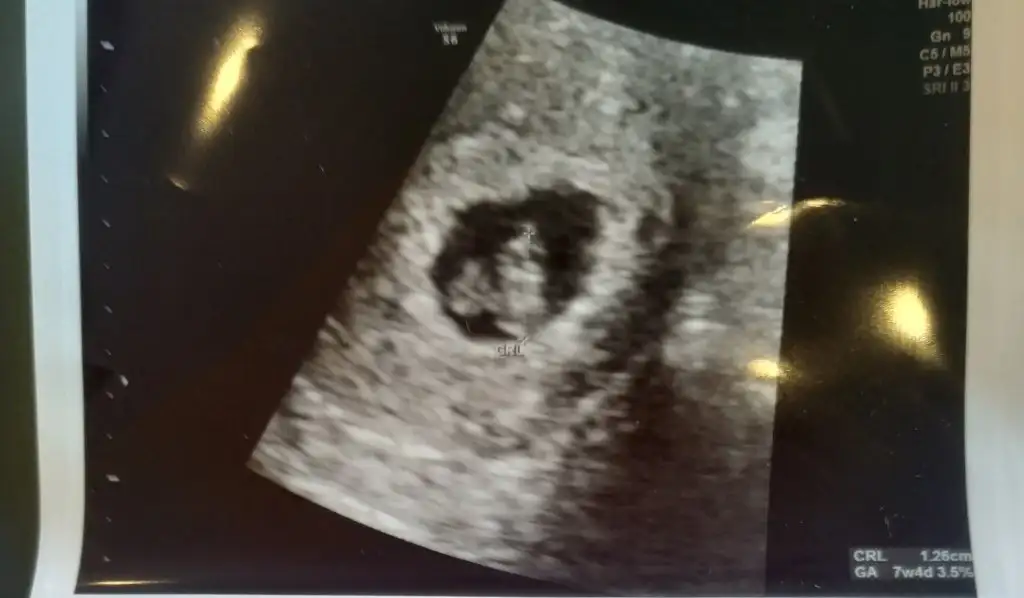

MasaAllah Rabbim saglikla kucagina almayi nasip etsin canim.6. Haftada kese boyutun kac acaba?Arkadaşlar sizden biraz öndeyim diye 2 ultrason görüntüsünü de atıyorum.fikir olsun. İlki 8. Hafta diğeri 6. Hafta. Eki Görüntüle 2548836 Eki Görüntüle 2548837

Şimdi kaç haftalıksın canımArkadaşlar sizden biraz öndeyim diye 2 ultrason görüntüsünü de atıyorum.fikir olsun. İlki 8. Hafta diğeri 6. Hafta. Eki Görüntüle 2548836 Eki Görüntüle 2548837